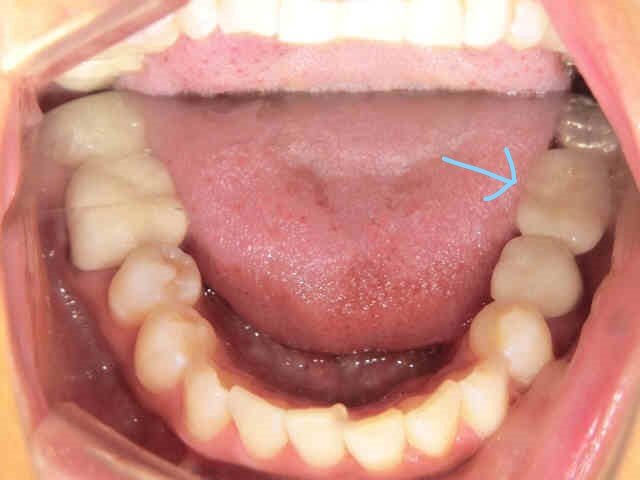

診査・診断の結果、麻酔下で慎重にブリッジを除去したところ、後方の歯が深い虫歯となっており、神経処置(抜髄)が避けられない状況でした。

その後、患者さまは「隣接歯に負担のかかるブリッジや入れ歯ではなく、インプラントによる治療を希望」され、左下奥歯部にインプラントとセラミック冠(メタルボンド)を用いた治療を実施しました(右下の写真参照/水色矢印部)。